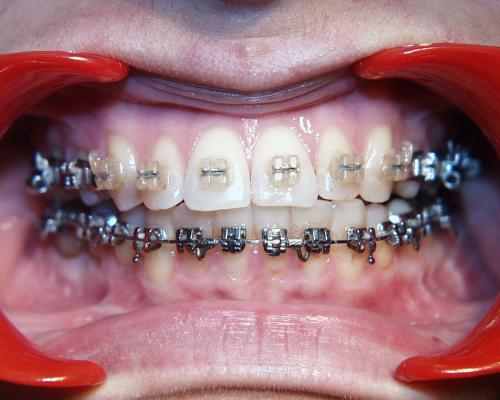

Während der Behandlung

Links Zustand beim Einsetzen der festen Zahnspange, rechts Situation unmittelbar nach der Operation (nach 2 Jahren, 4 Monaten). Der Unterkiefer wurde chirurgisch vorgesetzt und dadurch die Zahnreihen besser in Kontakt gebracht. Die Operation wurde an der Uniklinik Homburg durchgeführt. Eine Feineinstellung der Verzahnung ist aber im Laufe der kieferorthopädischen Nachbehandlung noch erforderlich.